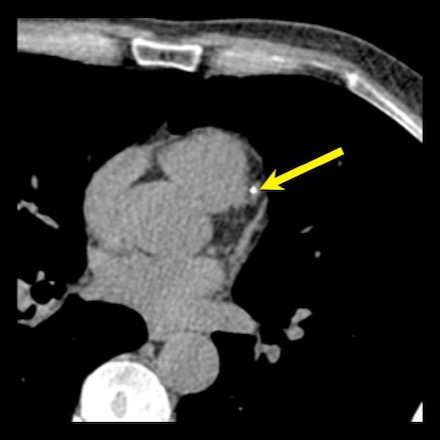

Another example of positive remodeling of a calcified plaque in the proximal LAD.

Again, the plaque is outward from the lumen causing no stenosis in the LAD.